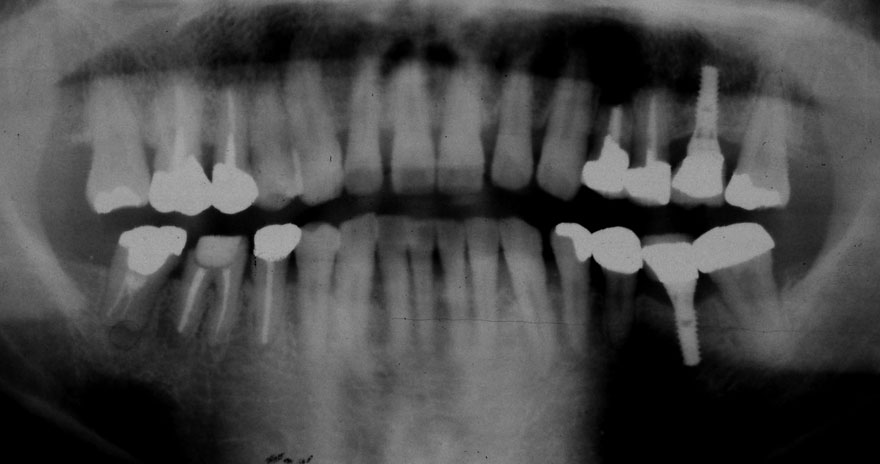

初診時 28歳 男性 平均歯槽骨喪失量:2.35mm

30年後 58歳

平均歯槽骨喪失量:3.88mm

22年間喪失量:-1.53mm

年間喪失速度:-0.05mm

(ケア頻度:2.80ヵ月ごと)